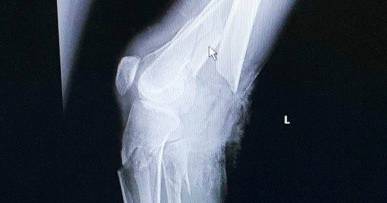

[size=1em]近日,江苏扬州一70岁老人,用高压锅煮粥,“服役”10年的锅突然爆炸,致左腿骨折,一度病危。